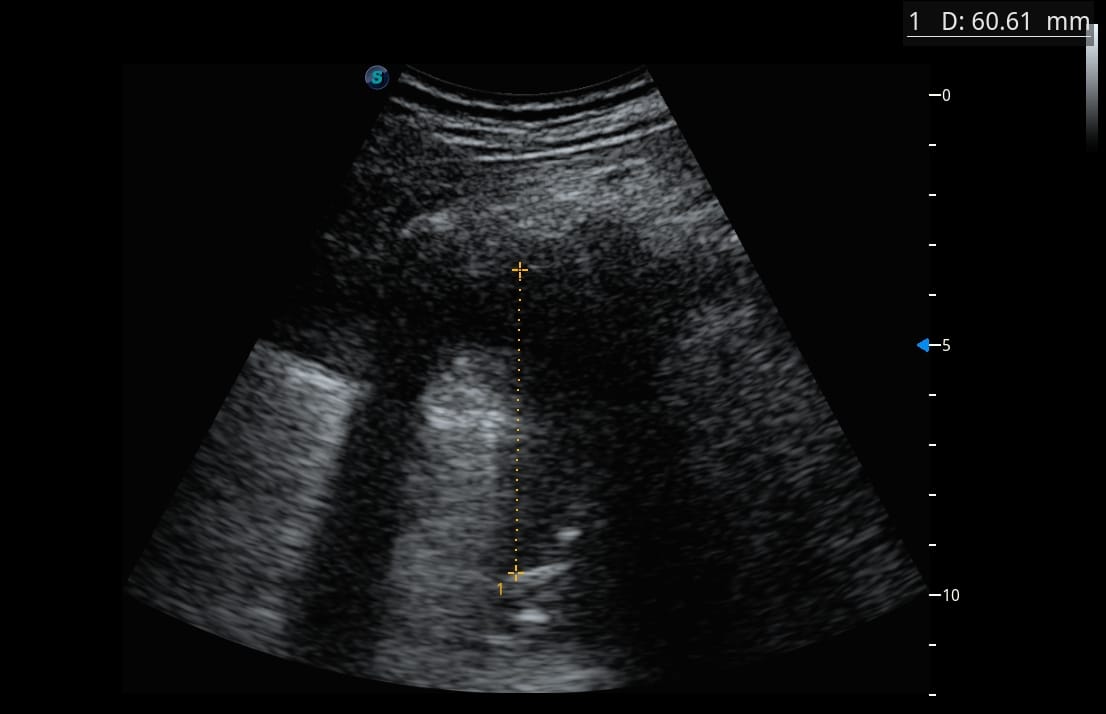

A droite

A gauche

Faites travailler votre œil et votre raisonnement avant la correction.

Quel est votre diagnostic ?

Analysez les images, repérez les éléments discriminants, puis confrontez votre hypothèse au raisonnement détaillé ci-dessous.

L’échographie pulmonaire va révéler des anomalies très marquées, en net décalage avec la clinique… avec des images particulièrement surprenantes du côté gauche.